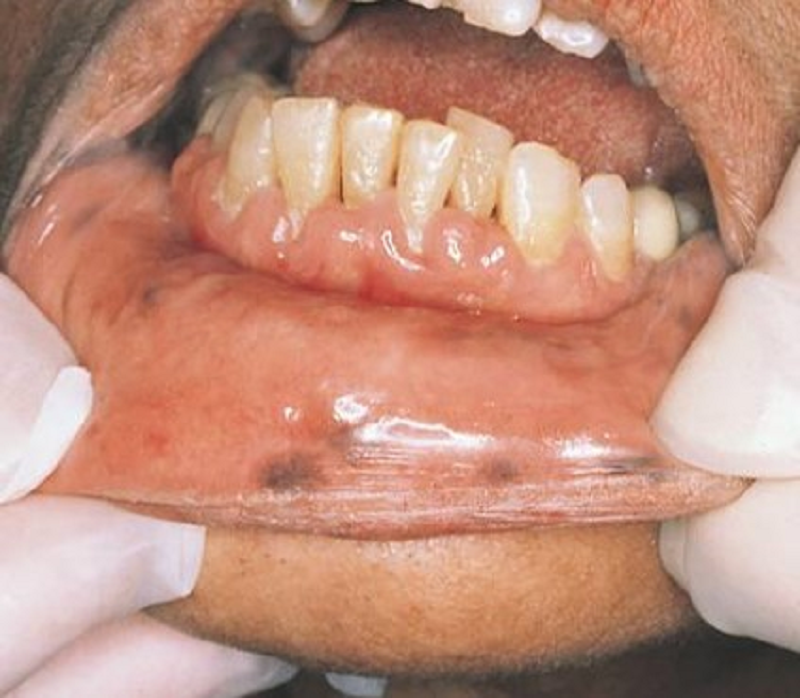

{"name":"Oral Path ID Chapter 6-9", "url":"https://www.quiz-maker.com/QPREVIEW","txt":"This condition is linked with Keratinosis of the palms of the hands & the soles of the feet. Individuals with this condition are likely to experience tooth mobility and premature tooth loss., This Term is used to describe The Appearance of type III (hypomaturation) Amelogenesis Imperfecta, Radiographs of a person with this condition appear to have a multilocular or “soap bubble” appearance","img":"https://www.quiz-maker.com/3012/CDN/92-4508546/final-pic-1.png?sz=1200"}